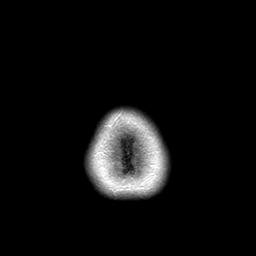

Metastatic bronchogenic carcinoma: T1-weighted MR -- Slice #23

[Home][Help][Clinical] Slice 23